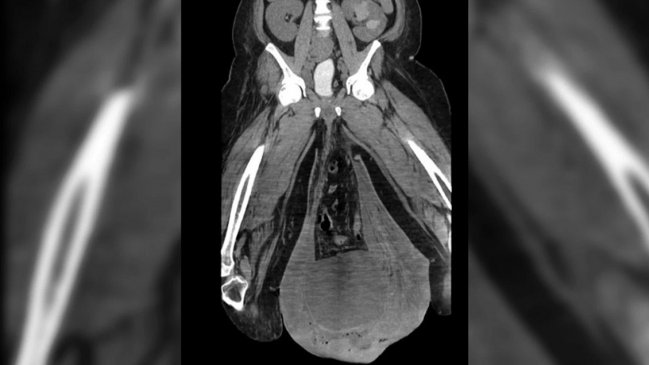

Un hombre de 43 años fue víctima de un extraño caso médico en que sus testículos se hincharon al punto de quedar del tamaño de pelotas de fútbol o de básquetbol.

El hombre había sido hospitalizado con fiebre y dolores cuando reveló su preocupante hinchazón: su escroto pesaba más de 3 kilos y le impedía hacer cualquier cosa con normalidad.

Los médicos determinaron que tenía una grave infección bacterial en los genitales debido a mala higiene.

Ante ello, tuvieron que someterlo a cirugía plástica en la zona, cortando todo lo que sobraba. Dos días después fue dado de alta y con sus genitales funcionando normalmente.